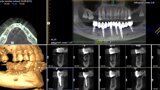

Natychmiastowa implantacja i zaopatrzenie protetyczne pacjentów z zaawansowaną chorobą przyzębia